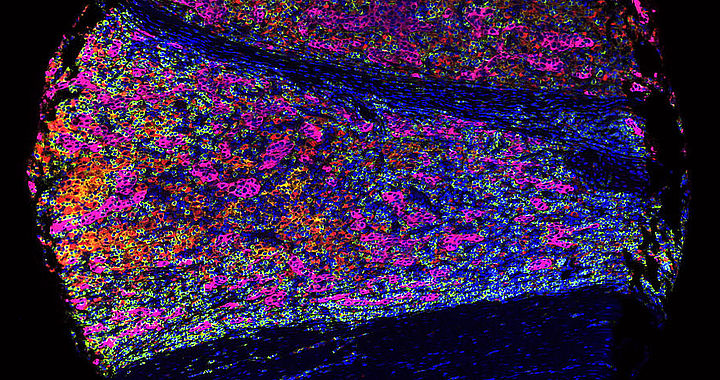

Methodisch stehen hier unter anderem das automatisierte Herstellen von sog. Tumormicroarrays, Multipleximmunhistochemie, Fluoreszenz-Scanning, Nächstgenerationensequenzierung (NGS) zur Verfügung.

Darüber hinaus besteht eine enge Zusammenarbeit mit Prof. Dr. Gernot Müller (Institut für Statistik und Rechnerbasierte Analysen). Mit Hilfe komplexer statistischer Analysen und Methoden der Künstlichen Intelligenz (KI) werden hier große Datensätze und hochaufgelöste Bilder analysiert.